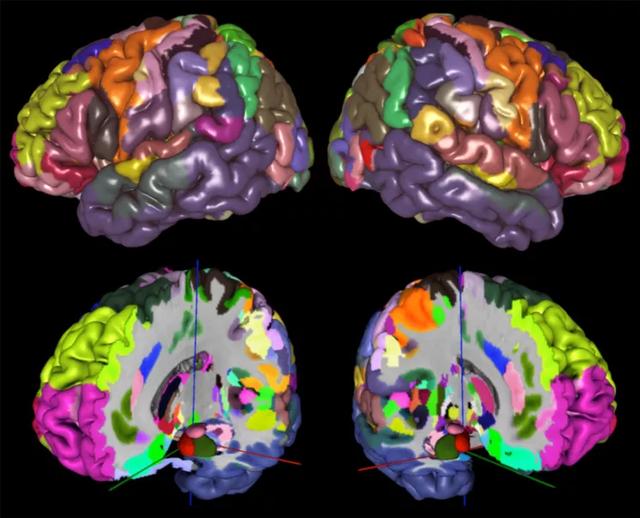

Julich脑图谱是基于23个人死后大脑的组织学切片获得的。经过41个项目,绘制出了人类大脑的248个细胞结构区域图(图1)。

图1:MNI-Colin27参考空间中Julich脑图谱的细胞结构最大概率图。